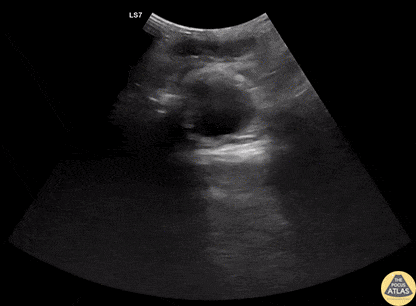

Trauma - Free Peritoneal Fluid from Splenic Injury

20s M presented with abdominal and back pain several hours after a fall off a ladder, and on FAST exam, had a large amount of free fluid seen in the pelvis/lower abdomen and in the RUQ. He was slightly tachycardic but normotensive, so underwent CT of the abdomen/pelvis, which demonstrated a significant spleen injury which was managed by IR embolization. Dr. Greg Wiener, PGY3 Denver Health Residency in Emergency Medicine